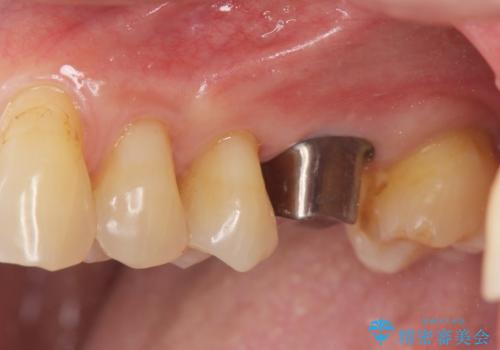

奥歯の欠損 インプラントによる咬合機能回復

治療症例の内容

- 50代男性

- 奥歯を失い噛めないことの治療を希望され来院されました。

臨在する歯が虫歯もなく健全であるため、ブリッジではなくインプラントを用いた機能回復を計画します。